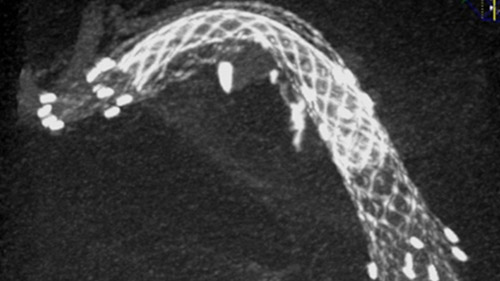

VasoCT visualizes small intra-cranial devices in vessel context with unmatched spatial resolution. Metal Artifact Reduction decreases streaking artifacts as from coil mass close to intra-cranial devices.